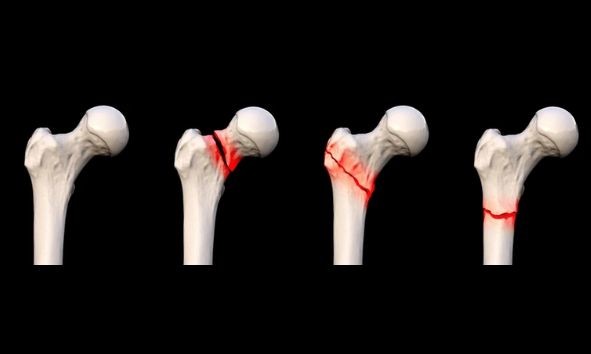

Fractures (simple and complex)

Open (compound) fractures

Most fractures heal in 6–12 weeks, depending on age, bone involved, and severity.

Delayed treatment can lead to poor healing, deformity, stiffness, and chronic pain.